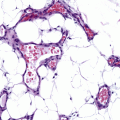

Fig. 6.2

Histopathological findings of skin lesions. NT littermates (a) have normal epidermal thickness with rare mononuclear cells. The skin of EL IL-4 Tg mice demonstrates mild spongiosis and acanthosis, with mononuclear cell infiltrate (b). LL mice demonstrate characteristics of chronic inflammatory lesion, with prominent hyperkeratosis and dermal mononuclear infiltrate, spongiosis and focal areas of parakeratosis (c). Mast cell degranulation (d) and eosinophil infiltrates (e) are also prominently present in chronic lesions. Hematoxylin & eosin (a–c, e). Geimsa (d) (Reproduced with permission, Chan et al. [35])